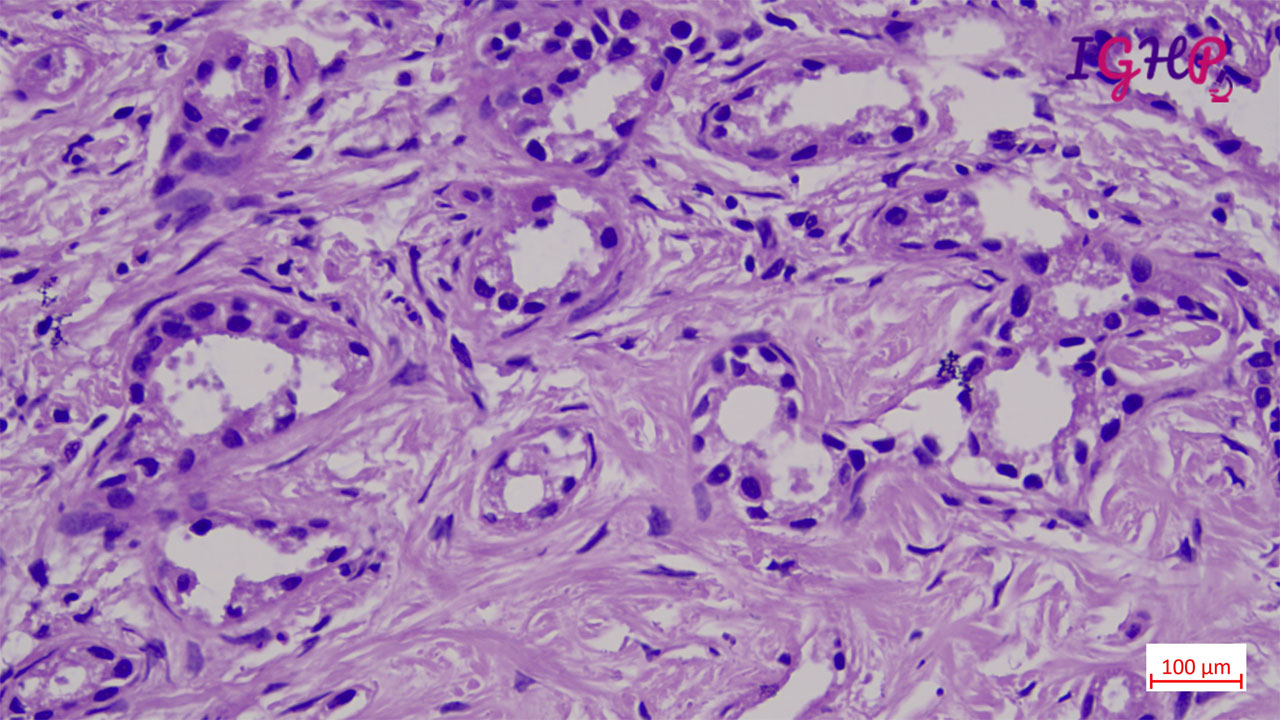

Microscopic examination showed an unencapsulated proliferation of uniformly spaced ductules lined by bland, cuboidal epithelium in a collagenous stroma. The architecture seems non-infiltrative, with evidence of entrapped native portal tracts present within the lesion itself.

BDA is an important diagnosis in frozen section examination. This needs to be differentiated from malignant nodules. Peripheral subcapsular location, presence of portal tracts within the lesion, inflammatory infiltrate and mild atypia favours a bile duct adenoma. Immunohistochemistrywith lowKi67 and wild type p53 may be used as adjunct.